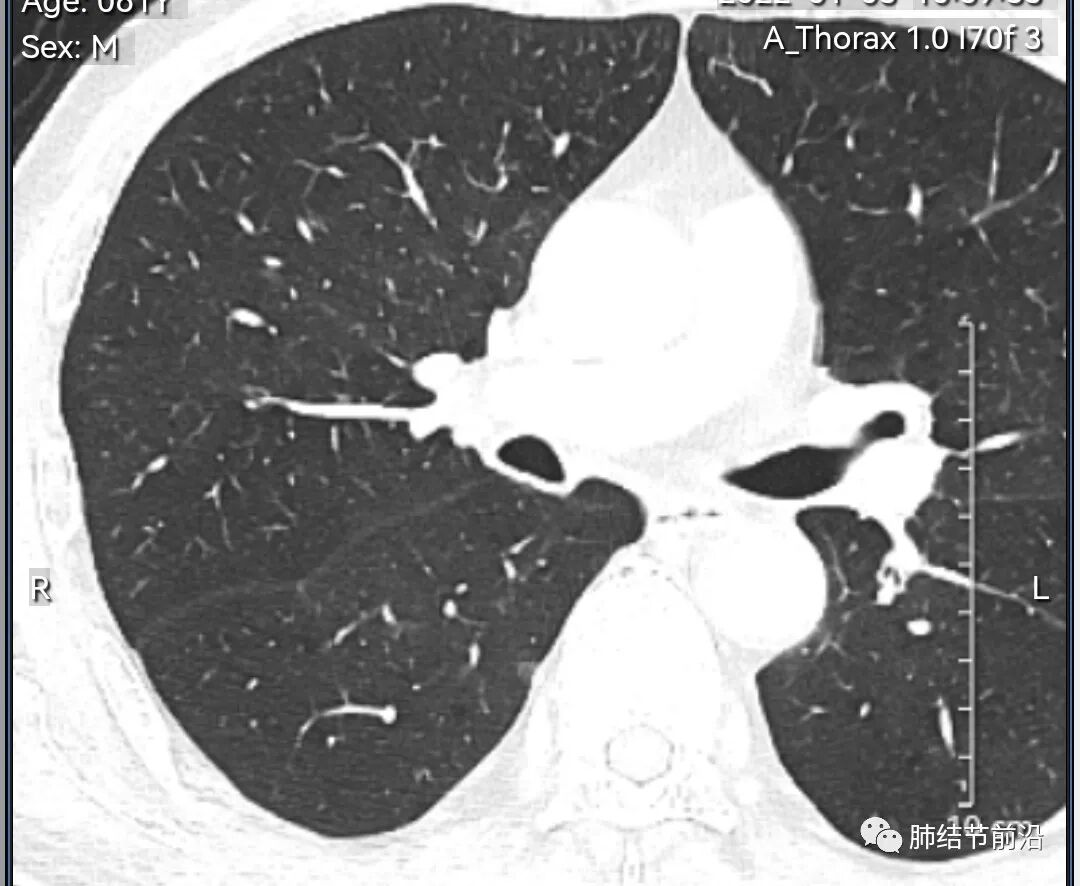

男性,67岁,重度吸烟史。CT发现右下肺囊腔。来看一下这个CT的特点:

该囊腔形态非常有特点,和常见的圆形肺大泡有很大的区别。

1.囊腔中央实性成分,周围有磨玻璃影。

2.囊腔中央有血管。

3.囊腔外周有分叶形态。

4.囊腔有胸膜牵拉。

出现这几种形态,CT可以确认恶性的腺癌。这个囊腔形成的机制,为肿瘤实性成分堵塞细支气管形成活瓣,肺泡内压力增高破裂行成,因此肺内血管成分保留。由于肺泡压力增高,而呈分叶状。另外,也有肿瘤的胸膜牵拉这一特点。

囊腔周围磨玻璃+囊腔中央血管为特征性表现。如果持续存在,几乎可以100%确认为早期肺腺癌。